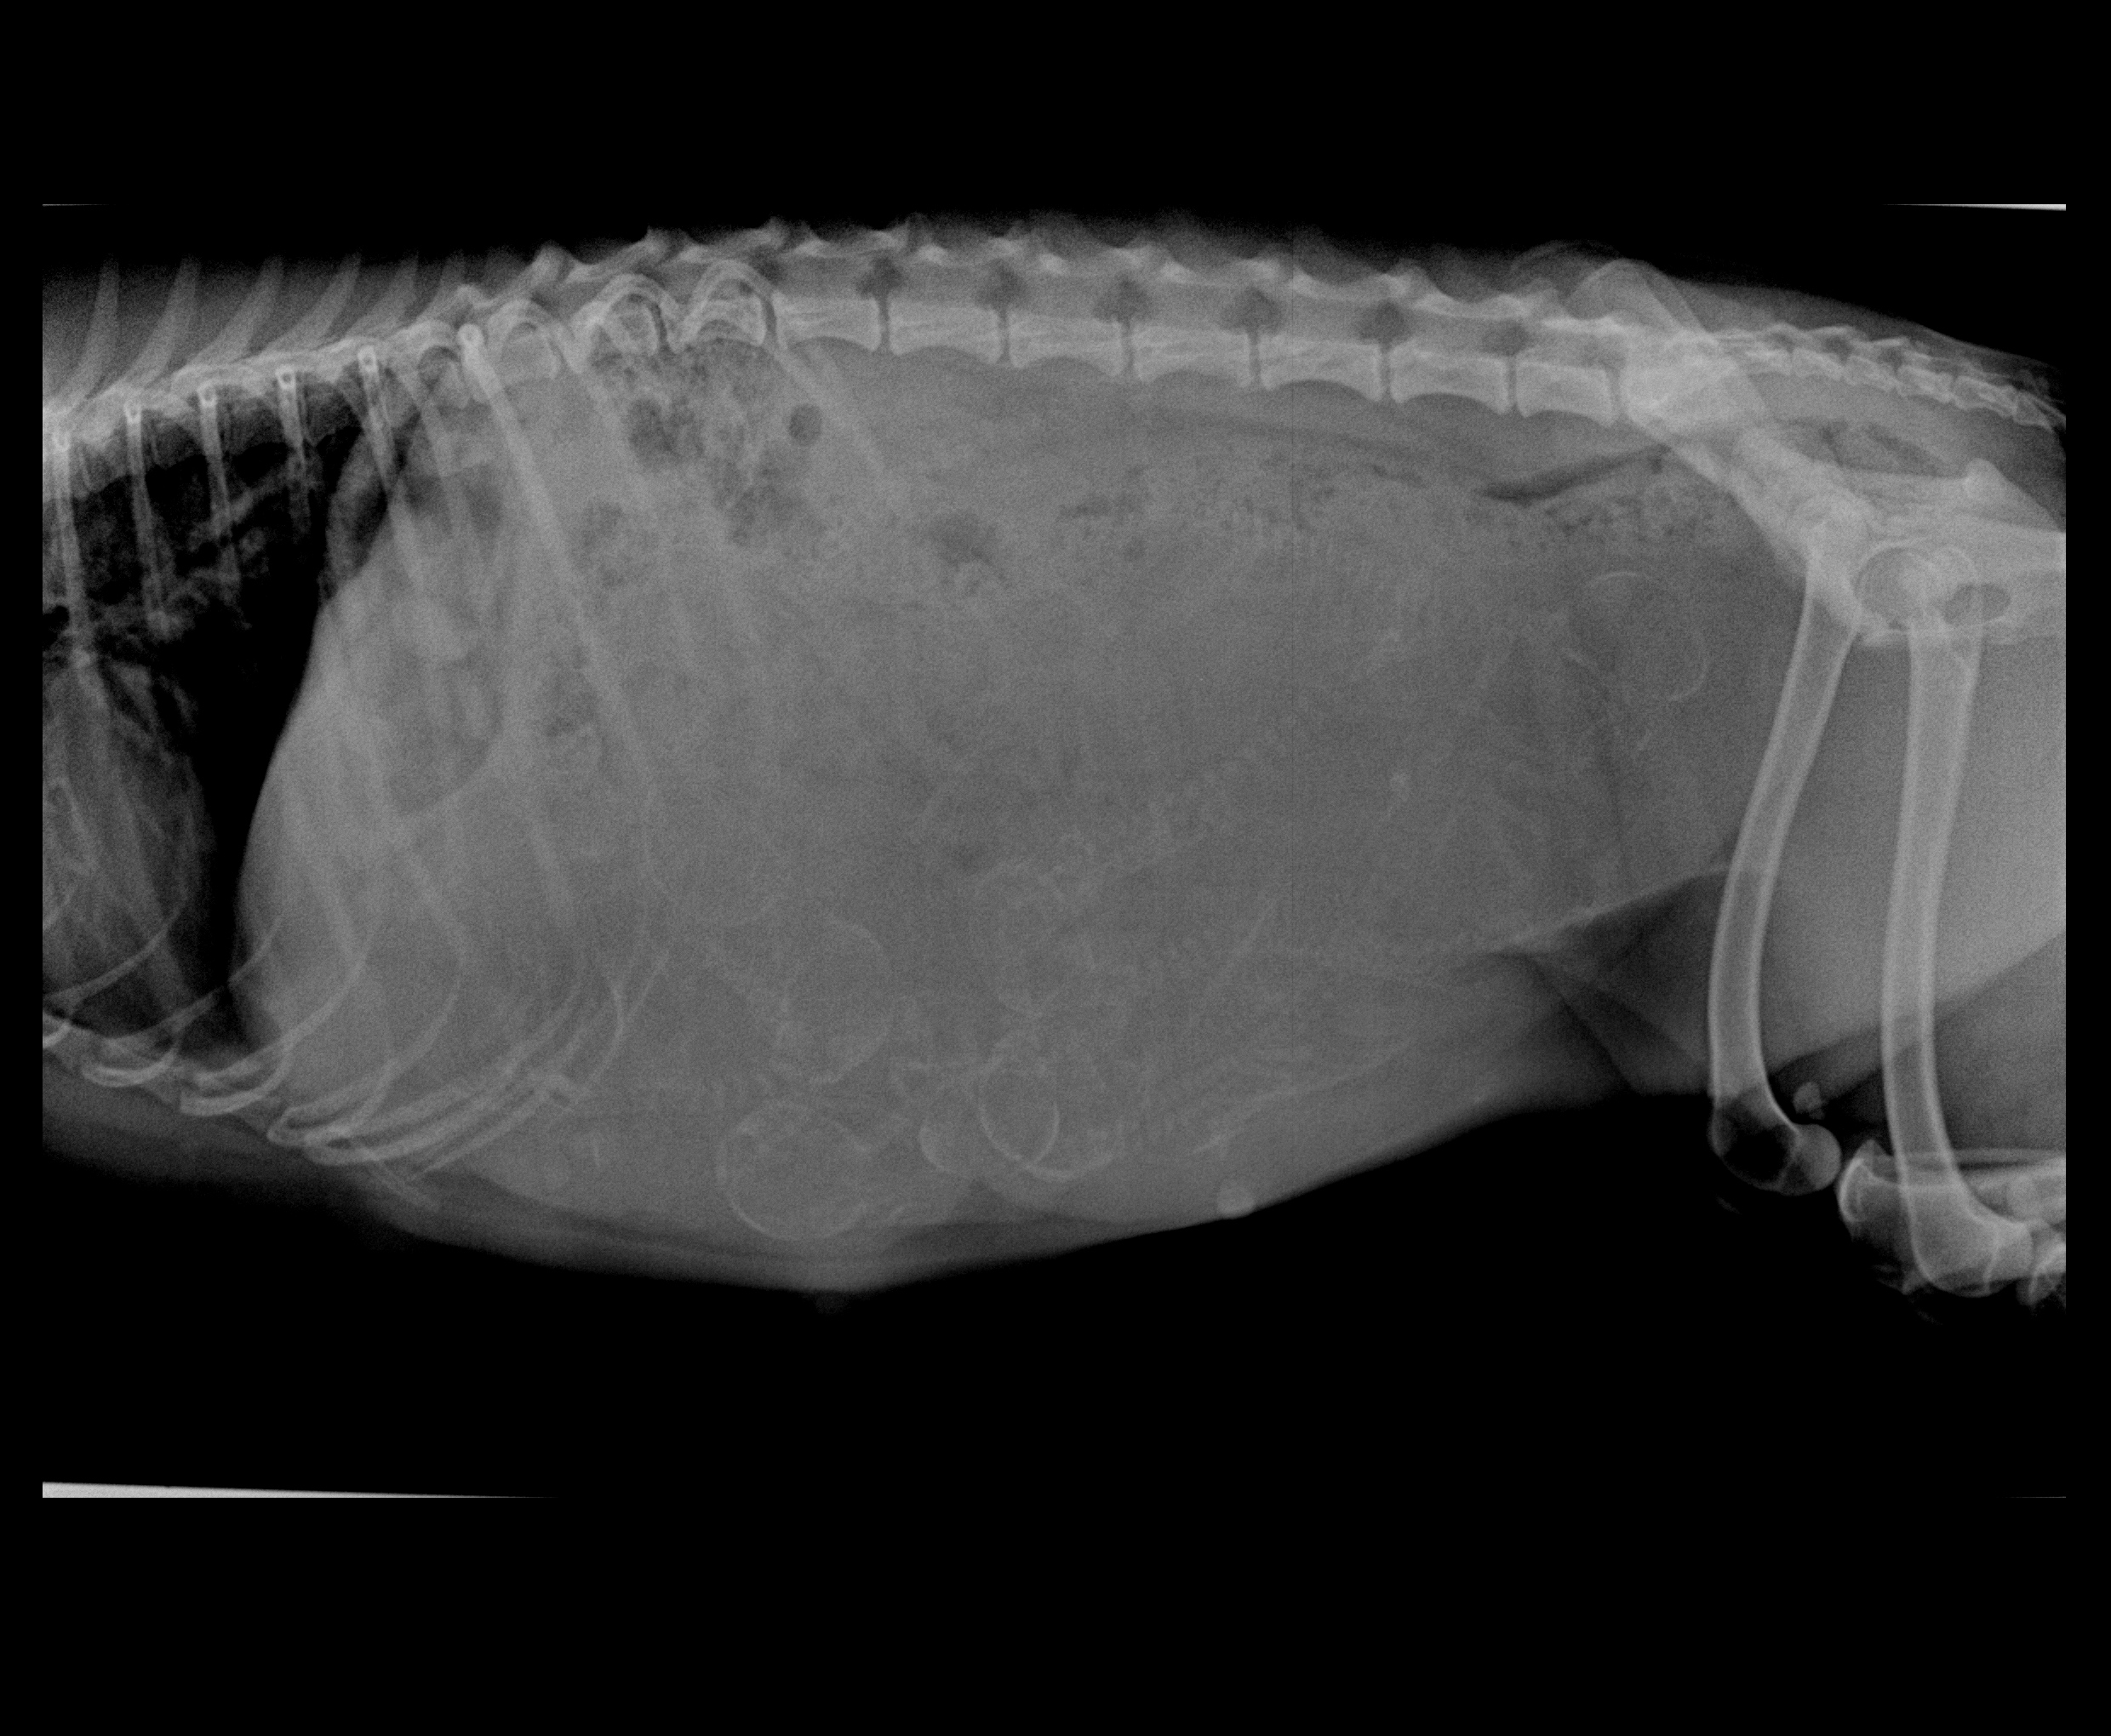

Sandy Preg xray preg i with Blaze 2

How many pups can you count? Hint look for heads :)